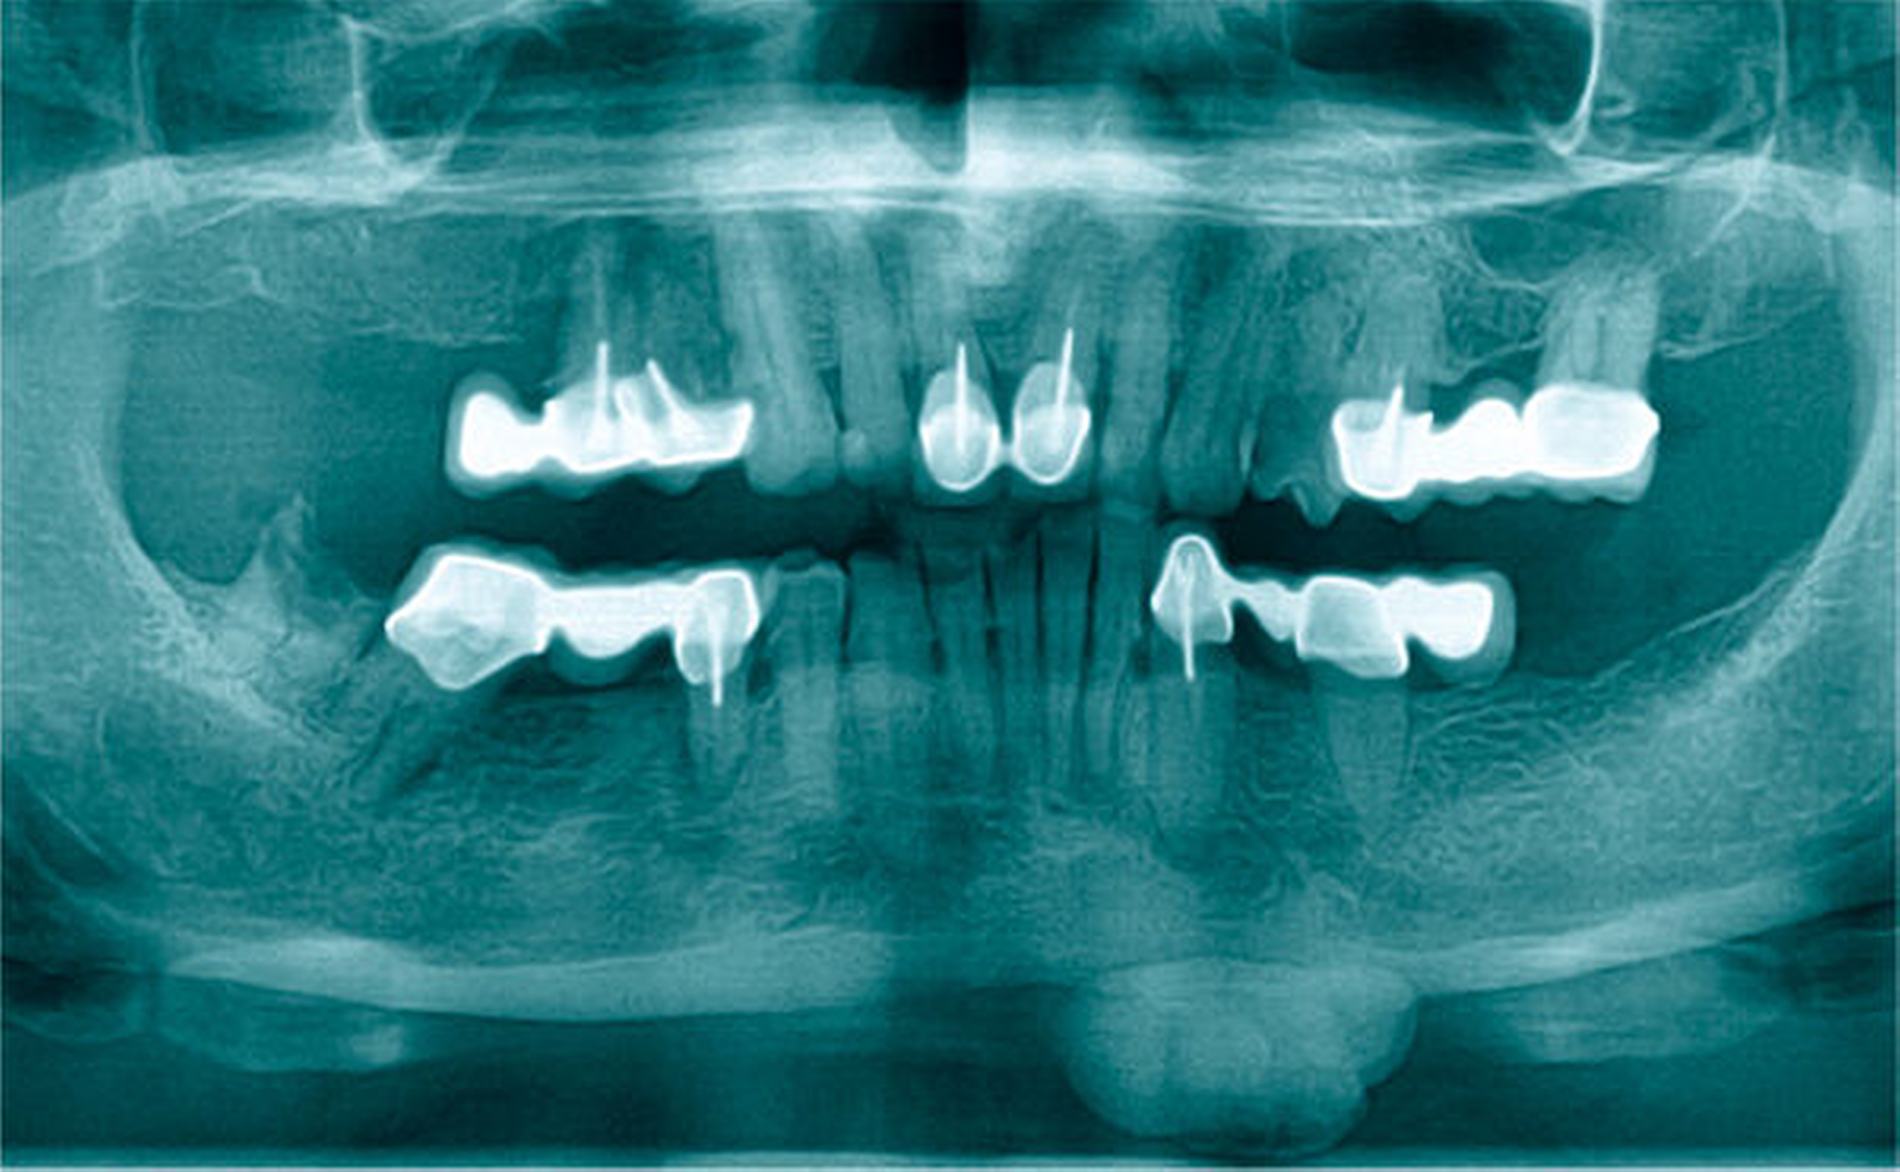

Im Rahmen der klinischen Untersuchung zeigte sich eine nicht-druckdolente, circa 2 cm x 2 cm große, solide, nicht-verschiebliche, knochenfeste Raumforderung submental links (Abbildung 1). Eine alio loco angefertigte Panoramaschichtaufnahme (PAN) zeigte eine knochendichte, scharf begrenzte Verschattung am links-frontobasalen Rand des Corpus mandibulare regio 31 bis 34 (Abbildung 2). Ein dentoalveolärer Zusammenhang konnte in der Zusammenschau von Klinik und radiologischem Befund ausgeschlossen werden.